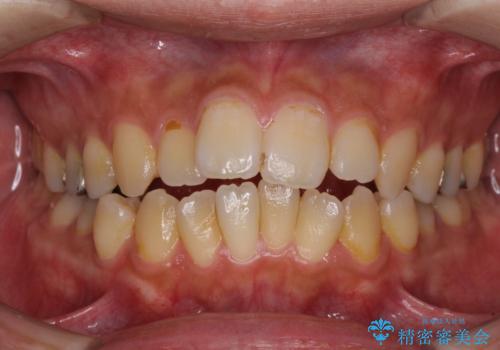

[ 前歯開咬 ] 前歯が噛んでいない マウスピース矯正治療

![[ 前歯開咬 ] 前歯が噛んでいない マウスピース矯正治療の症例 治療前](https://seimitsushinbi.jp/wp/wp-content/uploads/2022/11/IMG_4669-500x350.jpg?v=1668218426)